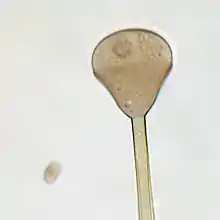

Apophysomyces variabilis resembles the other three members of the genus Apophysomyces but is characterized by the variable appearance of its sporangiospores and sporangiophores which range from club-shaped to trapezoidal to flattened spheres. The sporangiophore can measure up to 400 μm in length and has a funnel-shaped apophysis or swelling below the columella. Hyphae are smooth-walled, aseptate, and branched.[4]

Unlike most members of the Mucorales, Apophysomyces species often fail to sporulate under standard clinical laboratory culture conditions. These fungi require Czapek's agar (CZA), a nutrient-defined medium.[2] Colonies grow rapidly at 37 °C on CZA and initially appear white and woolly becoming greyish brown with age.[4][7][6] Colonies are grey and floccose, will grow on the lid of the petri dish, and are colourless on reverse.[8] Sporangiosphores are unbranched, smooth-walled, and light brown.[4] Sporangia are apophyseal, pyriform, beginning as whitish and turning brown with maturity. Sporangiospores are variable in size and shape.[7] Sexuality has not been observed in A. variabilis.[8]